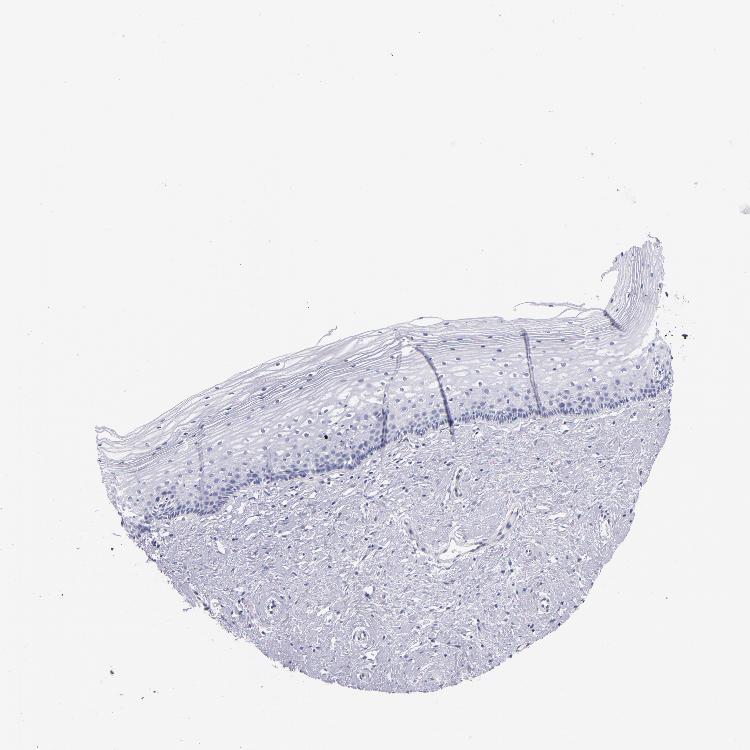

CERVIX - Antibody stainingi

Antibody staining in the annotated cell types in the current human tissue is reported as not detected, low, medium, or high, based on conventional immunohistochemistry profiling in selected tissues. This score is based on the combination of the staining intensity and fraction of stained cells.

Each image is clickable and will lead to virtual microscopy that enables deeper exploration of all samples and also displays staining intensity scores, fraction scores and subcellular localization as well as patient and tissue information for each sample.

Antibody CAB002168

Glandular cells Not detected

Squamous epithelial cells Not detected